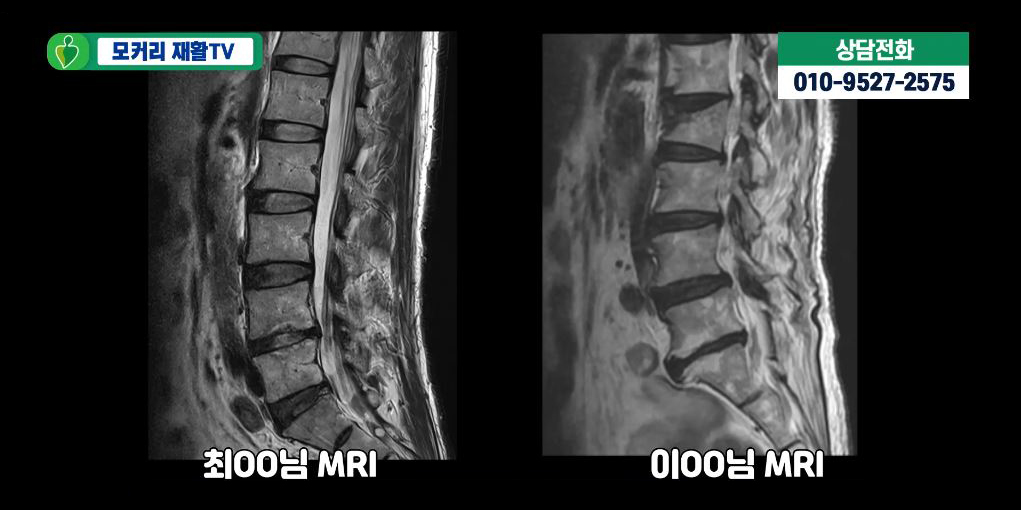

5. 네 번째 포인트 : 결과지에 없는 것도 중요하다

환자 입장에서 중요한 건 결과지에 적힌 것만이 아닙니다.

오히려 이런 질문을 스스로에게 해봐야 합니다.

- MRI에 나온 소견이

내 불편함을 전부 설명해 주는가? - 설명되지 않는 증상은 없는가?

- 그래서 추가 검사가 필요한 상황인가?

이 질문이 나올 때 의사는 종종 근전도 검사를 함께 고려합니다.